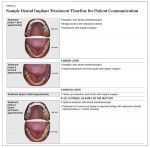

It is important to note to patients that all of the aspects of implant treatment are dependent on each other to achieve the desired goals in a predictable fashion. To ensure transparency and provide the best patient experience, patients should be informed of the approximate total treatment time and fees for all of the procedures associated with their selected treatment options. Providing a written timeline can help patients conceptualize the total treatment time involved, which is especially useful when planning and coordinating dental implant treatment for patients with busy schedules. Table 1 presents a sample treatment timeline with patient photographs and overlay drawings that was developed in presentation software and presented to a patient on a tablet computer.